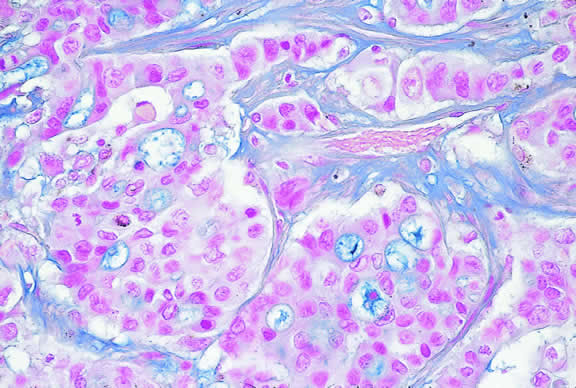

Microscopically, the uveal stroma is infiltrated by nest, cords, islands, and sheets of tumor cells whose general appearance and arrangement is dependent on the identity of the primary neoplasm. Most of the breast and lung tumors that metastasize to the eye are mucous-secreting adenocarcinomas. In such cases special stains such as Alcian blue, PAS, or mucicarmine are used to demonstrate the presence of intracytoplasmic mucin (Fig. 52). In most instances the pathologist can readily distinguish between a primary uveal melanoma and metastatic carcinoma in routine sections. Immunohistochemistry may be helpful in exceptional cases. Carcinomas are distinguished by positive immunoreactivity for epithelial markers such as cytokeratins and epithelial membrane antigen. Most melanomas stain with S-100 protein and vimentin and a variety of other markers including so-called melanoma specific antigen HMB-45, melan A, and microphthalmia factor. Occasionally, immunohistochemistry can confirm or provide clues to the identity of the primary tumor by demonstrating the presence of tumor specific antigens such as prostate specific antigen (PSA) in prostatic carcinoma or thyroglobulin in thyroid. Distinguishing between a primary uveal melanoma and choroidal metastasis from skin melanoma or another primary nonocular pigmented neoplasm may be challenging.197,198

Fig. 52. Mucin-secreting adenocarcinoma metastatic to the uvea. Alcian blue stain highlights mucin vacuoles in nests of tumor cells. (Alcian blue, × 100.)